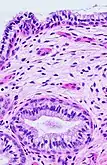

The endocervical mucosa is about 3 mm (0.12 in) thick and lined with a single layer of columnar mucous cells. It contains numerous tubular mucous glands, which empty viscous alkaline mucus into the lumen.[4] In contrast, the ectocervix is covered with nonkeratinized stratified squamous epithelium,[4] which resembles the squamous epithelium lining the vagina.[17]: 41 The junction between these two types of epithelia is called the squamocolumnar junction.[17]: 408–11 Underlying both types of epithelium is a tough layer of collagen.[18] The mucosa of the endocervix is not shed during menstruation. The cervix has more fibrous tissue, including collagen and elastin, than the rest of the uterus.[4]

.jpg.webp) The squamocolumnar junction of the cervix, with abrupt transition: The ectocervix, with its stratified squamous epithelium, is visible on the left. Simple columnar epithelium, typical of the endocervix, is visible on the right. A layer of connective tissue is visible under both types of epithelium.

The squamocolumnar junction of the cervix, with abrupt transition: The ectocervix, with its stratified squamous epithelium, is visible on the left. Simple columnar epithelium, typical of the endocervix, is visible on the right. A layer of connective tissue is visible under both types of epithelium. Transformation zone types:[19]

In prepubertal girls, the functional squamocolumnar junction is present just within the cervical canal.[17]: 411 Upon entering puberty, due to hormonal influence, and during pregnancy, the columnar epithelium extends outward over the ectocervix as the cervix everts.[15]: 106 Hence, this also causes the squamocolumnar junction to move outwards onto the vaginal portion of the cervix, where it is exposed to the acidic vaginal environment.[15]: 106 [17]: 411 The exposed columnar epithelium can undergo physiological metaplasia and change to tougher metaplastic squamous epithelium in days or weeks,[17]: 25 which is very similar to the original squamous epithelium when mature.[17]: 411 The new squamocolumnar junction is therefore internal to the original squamocolumnar junction, and the zone of unstable epithelium between the two junctions is called the transformation zone of the cervix.[17]: 411 Histologically, the transformation zone is generally defined as surface squamous epithelium with surface columnar epithelium or stromal glands/crypts, or both.[20]